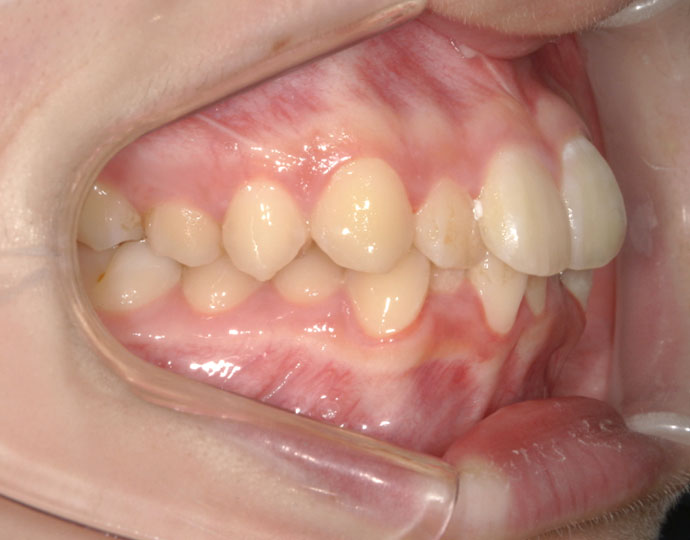

治療前

| 患者様 | 女性 18歳 |

| 主訴 | 歯並びを綺麗にしたい。 |

| 診断 | 叢生歯列不正咬合 |

| 治療方針 | 上下顎左右第一小臼歯の抜歯(計4歯) |

| 治療に使用した装置 | セルフライゲーションブラケット(インタラクティブタイプ) |

| 治療期間 | 2年2カ月 |

| 治療回数 | 24回 |

| 治療費(自費診療) | 847,000円(税込み) |